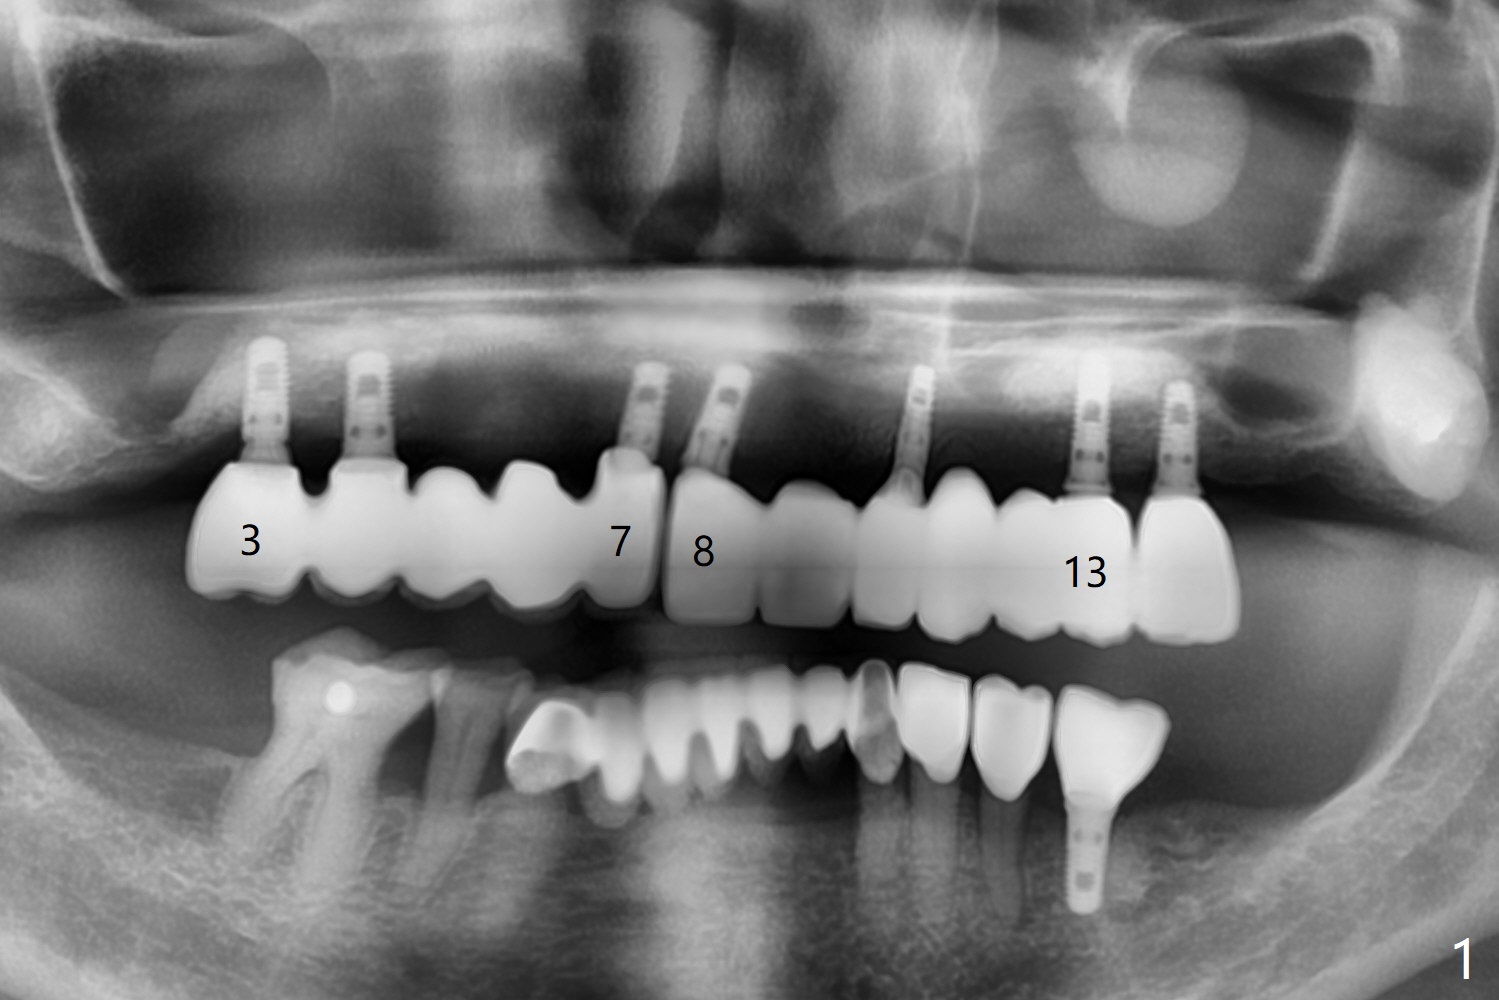

64岁女#3-7,8-13植牙桥多年,7-8之间出现间隙(图一),最近7颊侧牙龈出血,CT显示7颊侧骨板缺失(图二,三)。可能植骨有困难,似乎2x12毫米植体是解决问题部分措施(图四),接着外提升,在5,6上颌窦植骨,如果顺利,同期在6种植,2x10毫米(图五),3-5暂时改为悬臂桥,如果5提升成功,再种植一个植体。但是病人要求植骨。Return to Protect Graft 101 Xin Wei, DDS, PhD, MS 1st edition 05/12/2021, last revision 06/15/2021